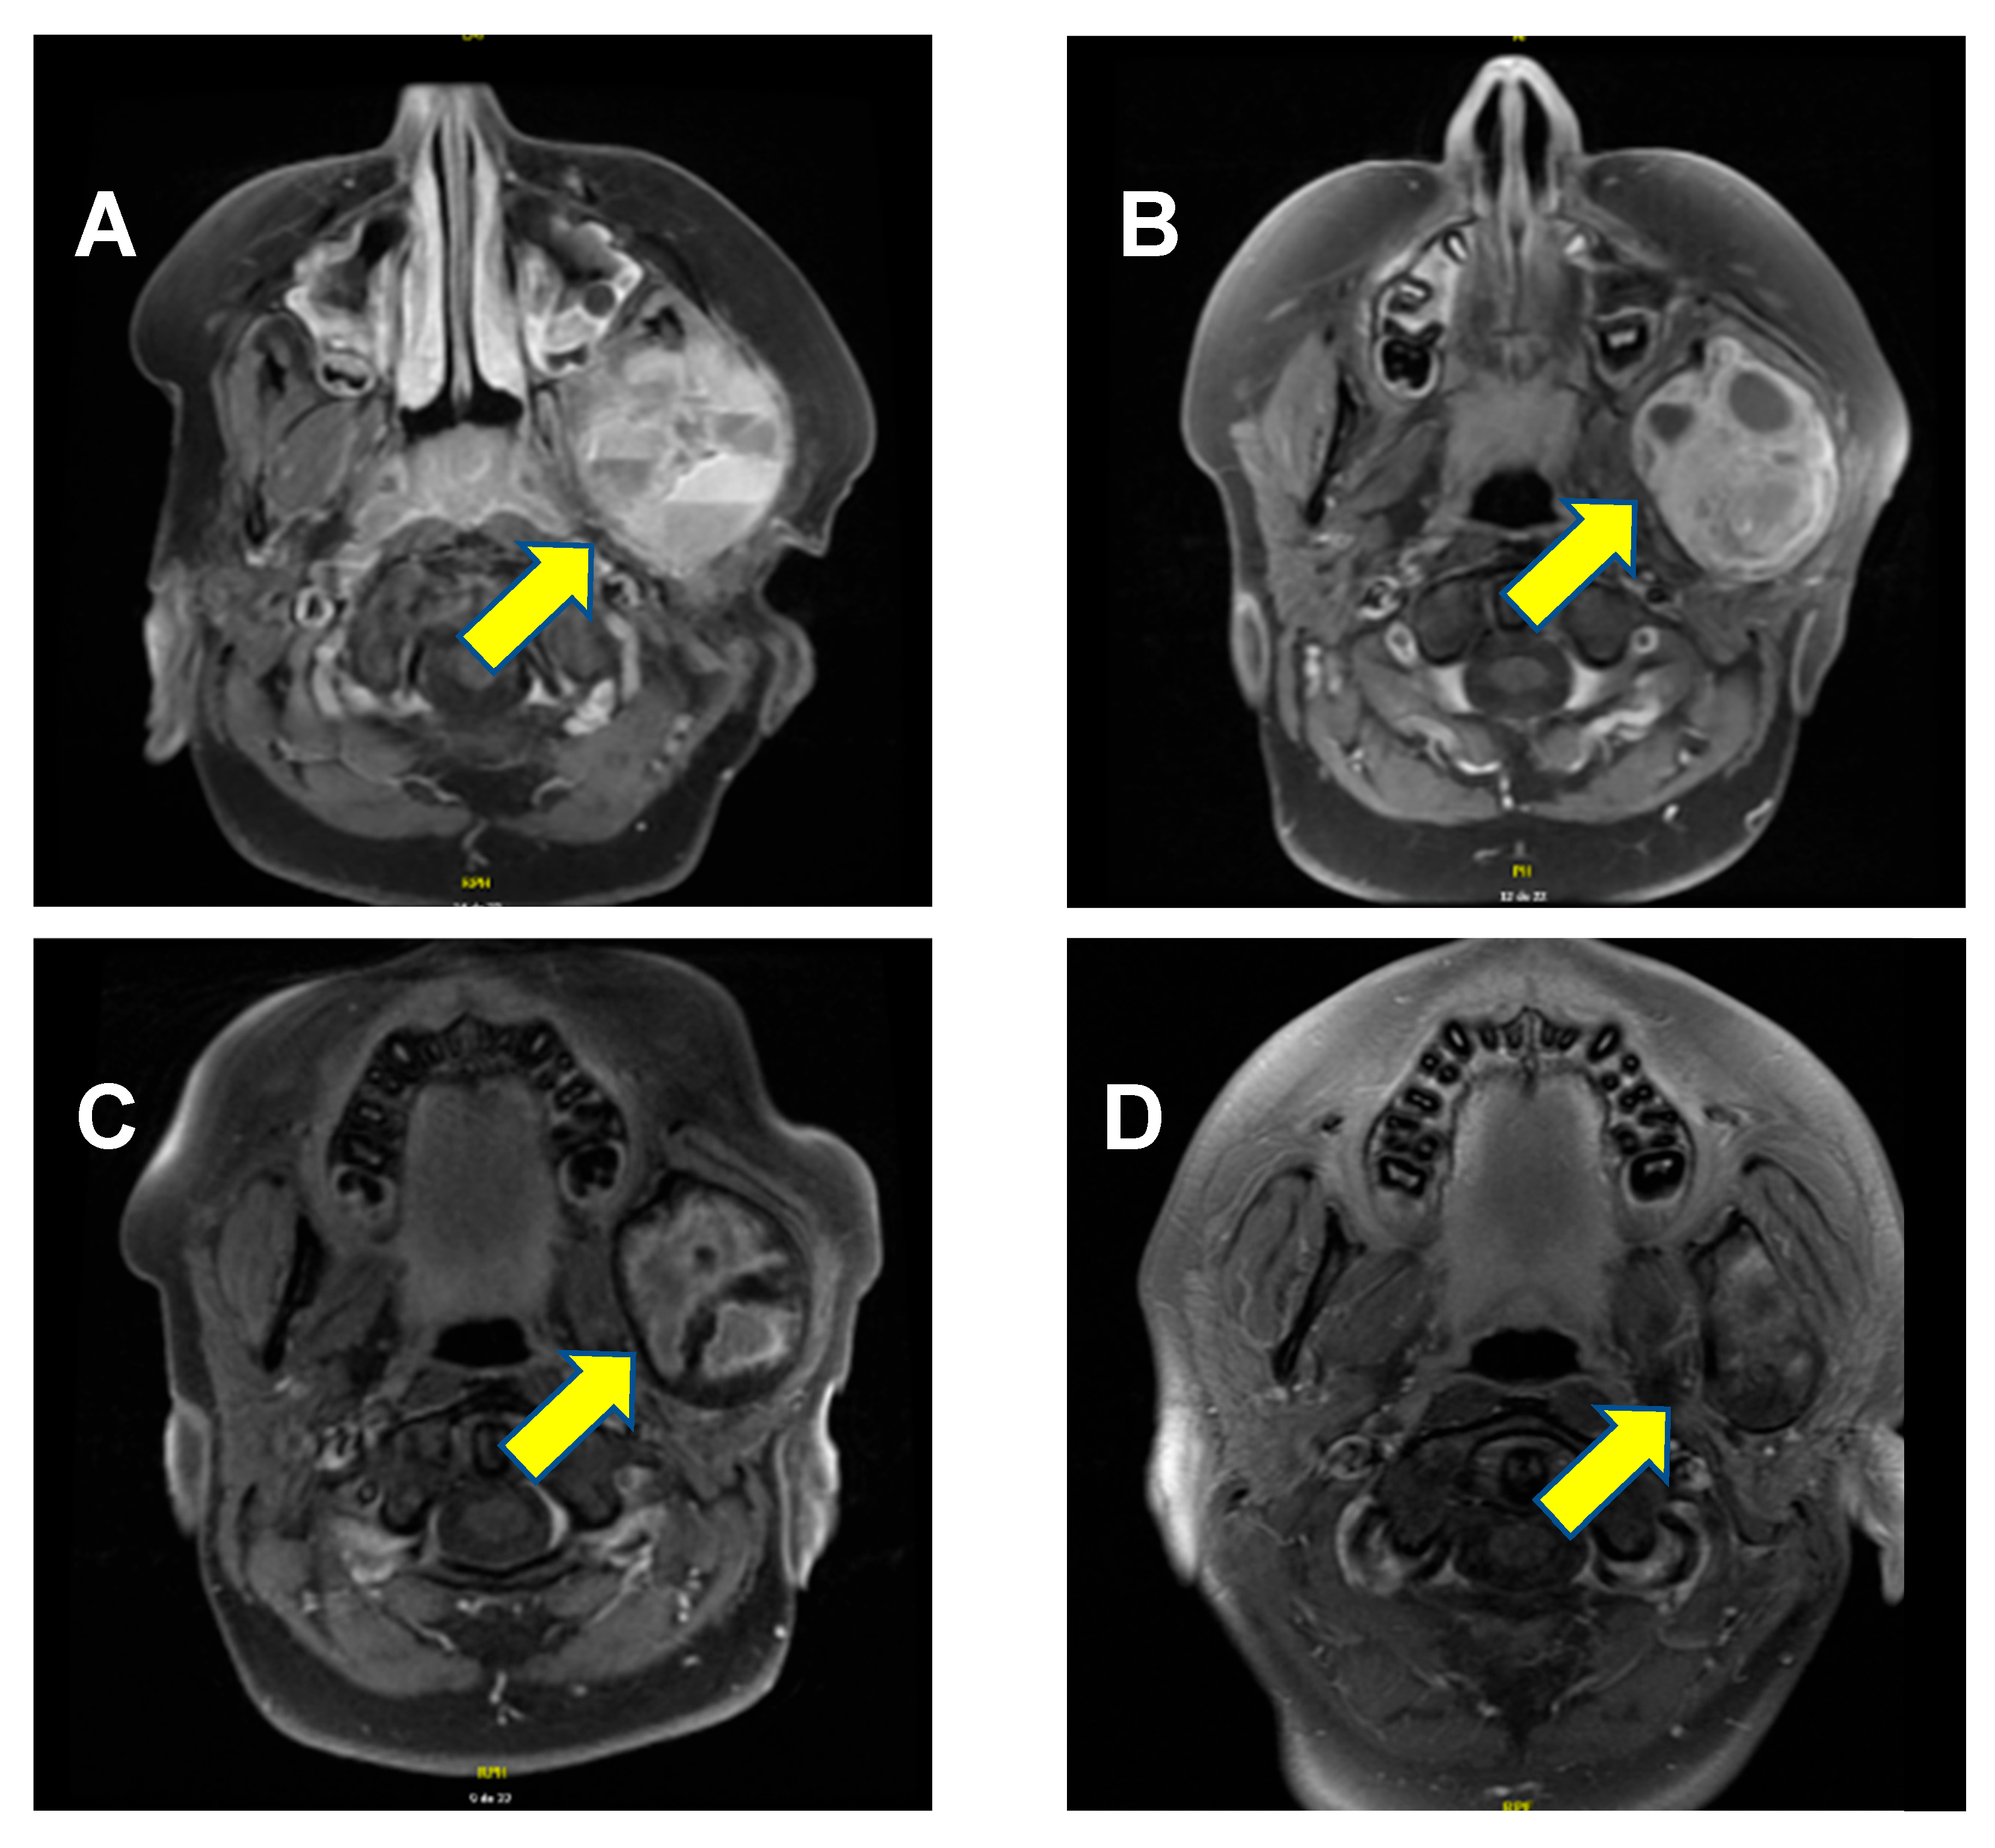

A previously healthy 9-year-old boy presented with worsening edema of the left cheek that had developed over the course of several months. The patient had a visible and palpable lesion on the left branch of the jaw, which was mildly tender upon pressure. The mass was firm, and there was erythema. Of note, there were no other significant symptoms such as swallowing difficulties or difficulty breathing or speaking. The patient’s past medical history was entirely unremarkable. Notably, there was no evidence of intrauterine growth restriction or prematurity, and there were no clinical signs or family history of rickets. A cervical magnetic resonance imaging (MRI) confirmed the presence of a lesion measuring 5.2 cm × 4.6 cm × 4.1 cm located on the ascending branch of the left mandible, including the mandibular condyle. It presented several cystic components, measuring up to 4 cm× 2.6 cm. The masseter, temporal, and pterygoid musculature were lightly infiltrated by the lesion (Figure 1A). A temporomandibular biopsy was performed. The histopathology analysis showed bone and fibrous hemorrhagic fragments with evidence of fusiform mononuclear cells, as well as several multinuclear osteoclast-like cells, confirming the diagnosis of an aneurysmal bone cyst.

Denosumab 2 mg/kg (120 mg) was administered subcutaneously once weekly for the first four weeks, then 2 mg/kg (120 mg) once a month for the subsequent sixteen months. This dose was selected based on previous experiences reported in the literature [10,11,12]. Supplementation therapy of calcium and vitamin D was given daily during the treatment to prevent hypocalcemia. Clinical response was rapid, with lesion pain resolution within a month. There was also a progressive decrease in the lesion’s dimensions after 17 months of treatment (Figure 1C).

Remarkably, the lesion continued to shrink even after denosumab discontinuation. At the most recent follow-up MRI, performed 26 months after treatment discontinuation, the lesion measured 4.3 cm × 2.6 cm × 3.5 cm, (Figure 1D). Most importantly, the significantly deformed malformation on the left aspect of the mandible is clinically no longer apparent; the aneurysmal bone cyst is meanwhile just barely palpable, and the patient no longer complains of any pain. A timeline of the patient’s clinical course, from initial discovery to lesion regression and symptom resolution, is provided in Figure 2.

From a therapeutic perspective, our patient exhibited an excellent response to denosumab, with persisting ongoing reduction in the mass 26 months after treatment discontinuation (Figure 1D). The fact that this initial deforming lesion is no longer clinically noticeable has had a significant impact on this child’s self-esteem and quality of life. Of course, close clinical monitoring and follow-up remain essential, as there are reports of tumor recurrence after denosumab discontinuation [31,32].

Figure 1. Axial T1-weighted MRI scan with gadolinium. (A) At diagnosis, a lesion of 5.2 cm × 4.6 cm × 4.1 cm was evidenced (arrow), containing multiple cystic components, with the bony cortex hard to establish and a relatively central enhancement. (B) Three months following the initiation of denosumab, the lesion measured 5.3 cm × 4.4 cm × 3.7 cm. The cystic components had diminished in size, enhancement appeared more important since the cystic parts were diminished, but the intensity of enhancement was similar. (C) About a month after administration of the last dose, the lesion measured 5.1 cm × 4.1 cm × 3.6 cm. Internal enhancement foci were still present, especially in the periphery. (D) Twenty-six months after treatment discontinuation, the lesion measured 4.3 cm × 2.6 cm × 3.5 cm. Post-contrast enhancement of signal anomalies was diminished on T2-weighting, showing that the radiological shrinkage of the lesion persisted.